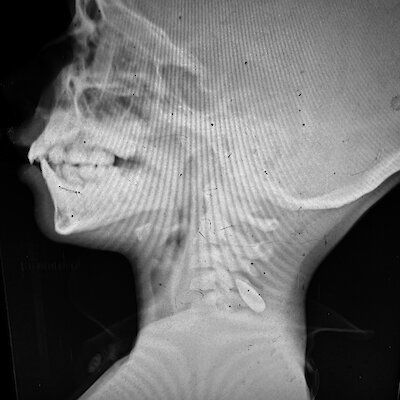

Систематические ранения других частей тела

Врач:ини также заметили, что в разные дни к ним поступали группы детей с ранениями одних и тех же частей тела — головы и шеи, груди, конечностей и так далее. Врач:ини предполагают, что это может быть скоординированная политика либо «игровой» характер ведения огня. Эти наблюдения совпадают с анонимными признаниями израильских солдат:ок в газете Haaretz о том, что они вели огонь по гражданским на пунктах раздачи продовольствия, называя это детской игрой «Соленая рыба» (аналог игры «Море волнуется раз»).